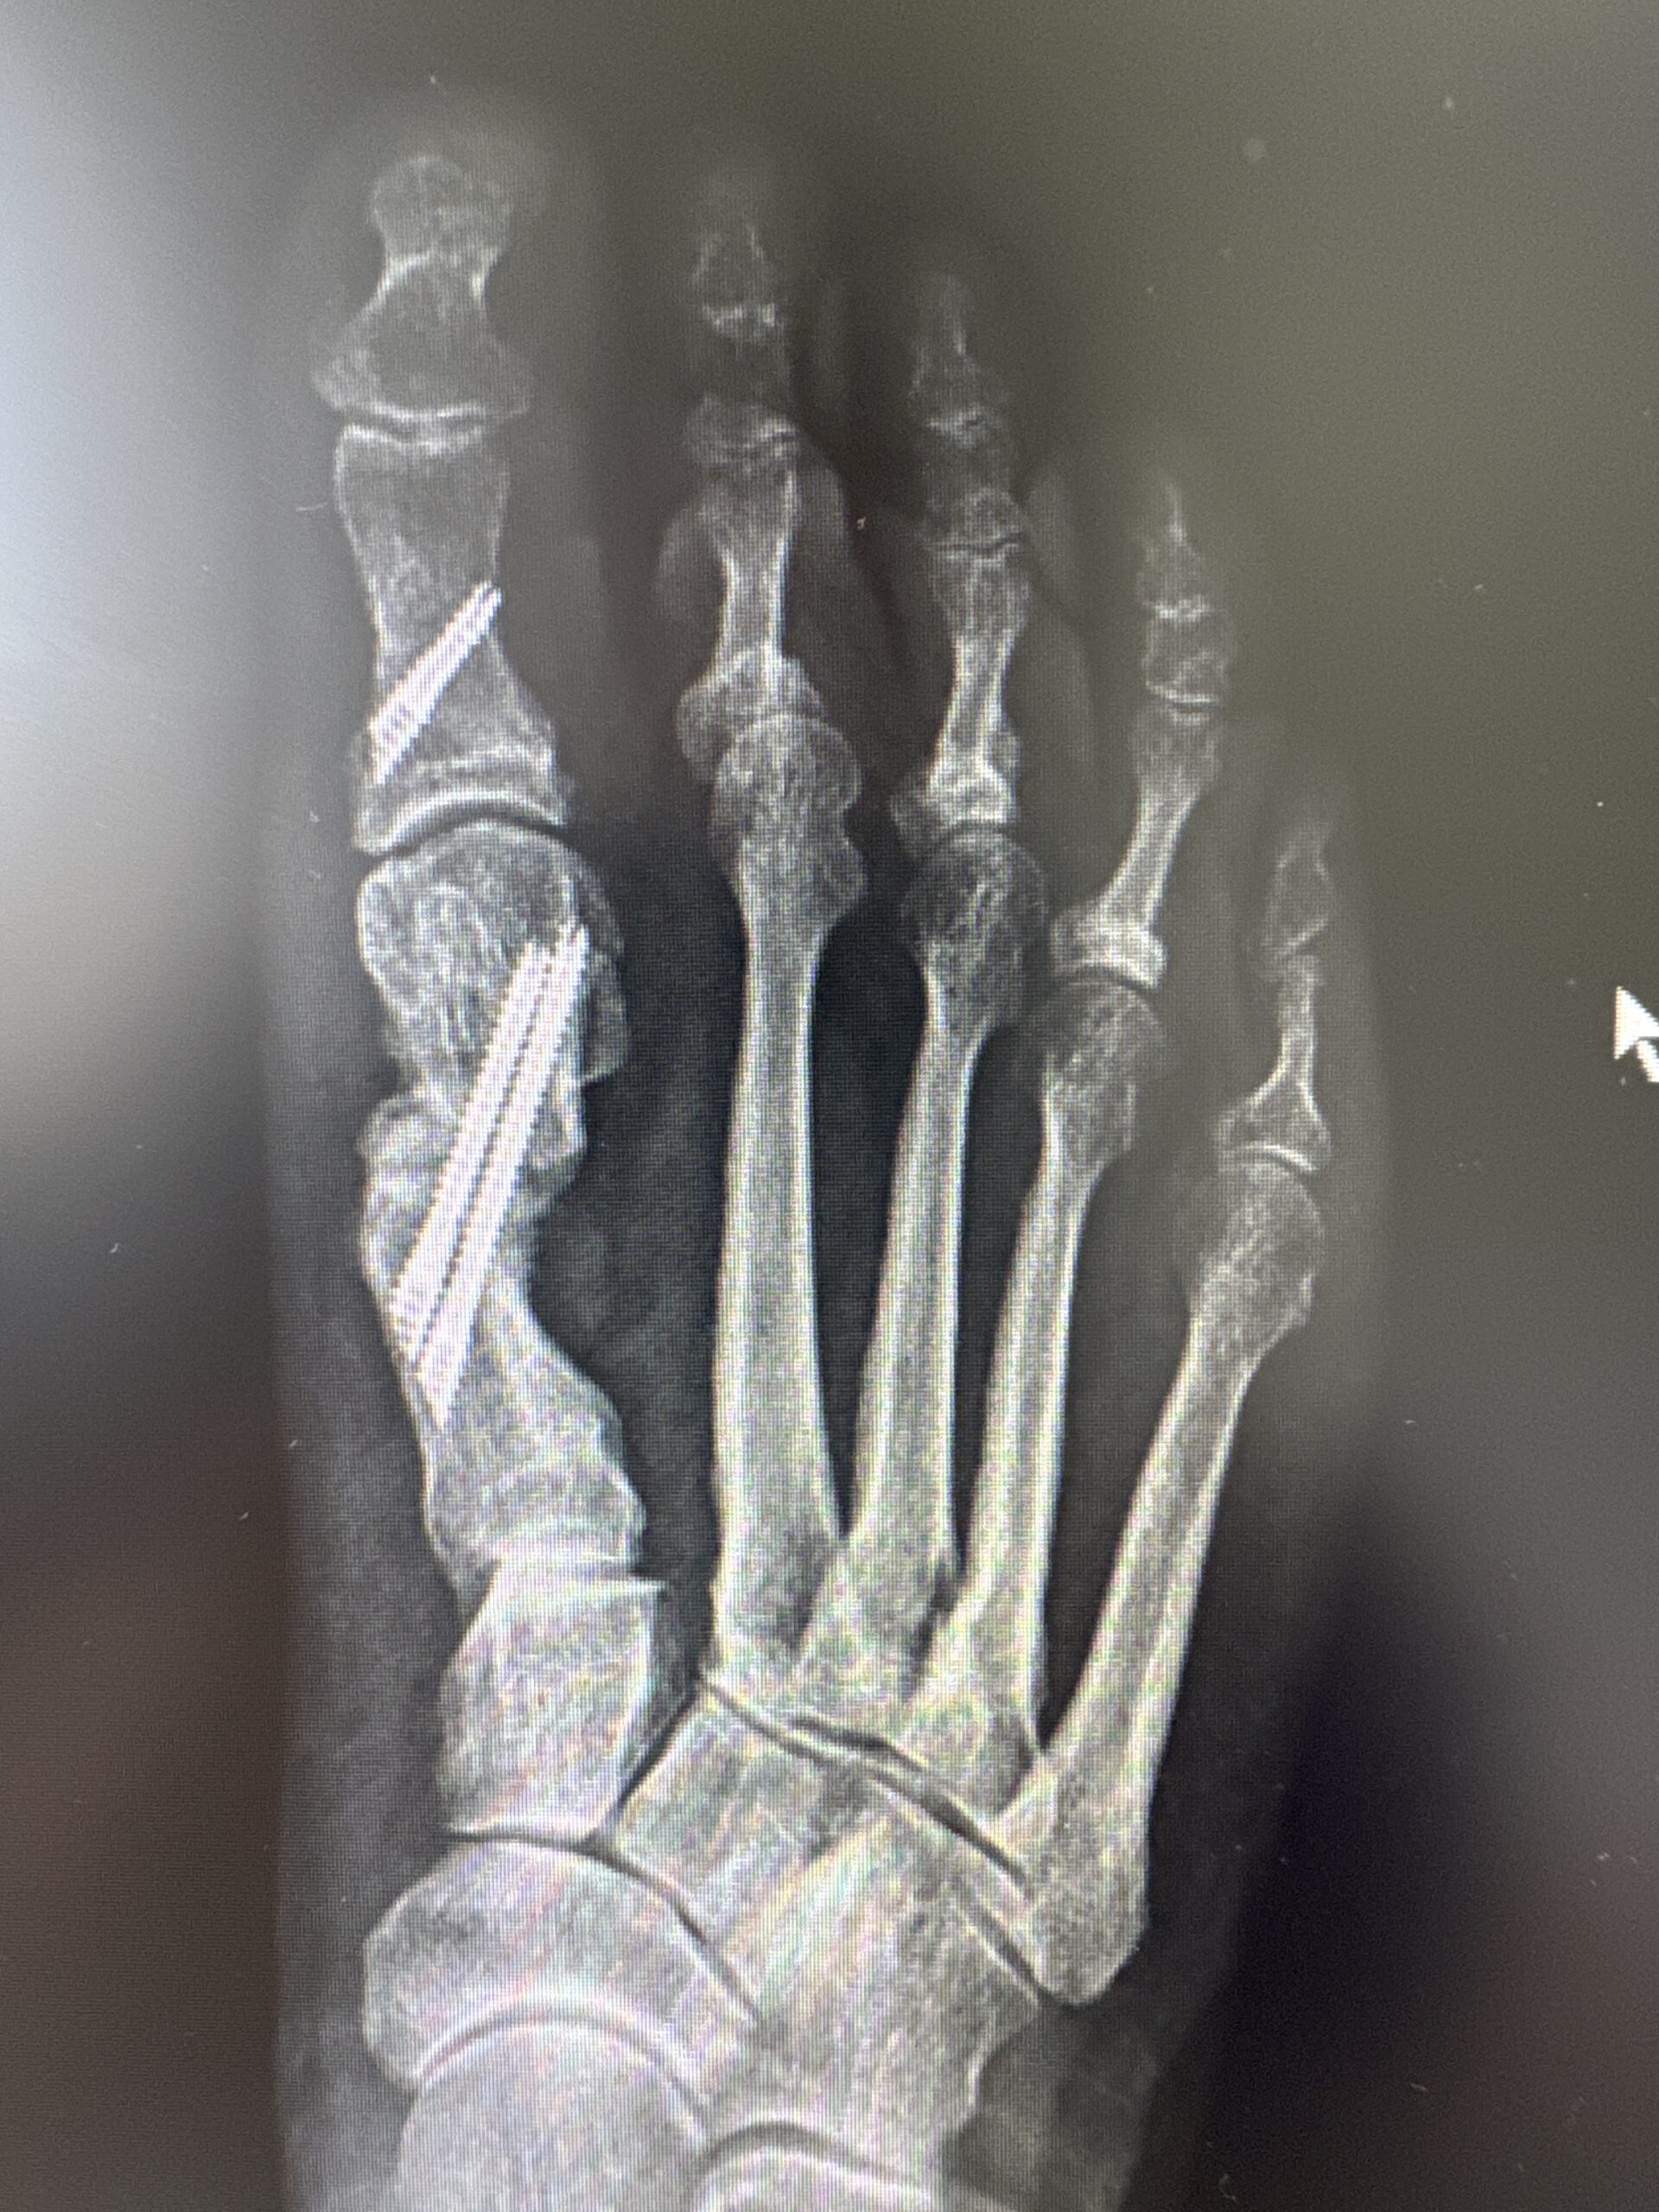

Os presento un caso de deformidad de hallux valgus intervenido con una técnica de cirugía percutánea de 3ª generación. En este ocasión, se ha realizado unas osteotomías en el primer metatarsiano y en la primera falange que se han fijado con tornillos que confiere a la corrección estabilidad, seguridad y menor dolor postoperatorio manteniendo el respeto a las partes blandas.

Los resultados radiográficos y clínicos los podéis ver en las fotos antes de la cirugía y los 3 meses de la misma.